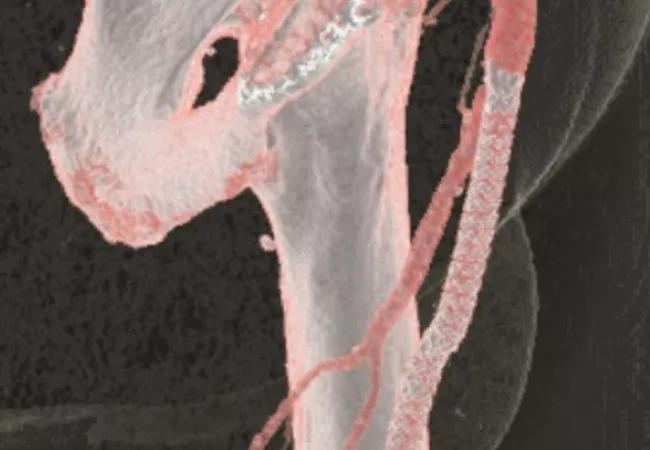

Imaging studies from patients with long femoropopliteal blockages treated with the fully percutaneous Detour procedure.

DETOUR I — a prospective, nonrandomized, single-arm investigation — evaluated fully percutaneous femoropopliteal bypass in patients with blockages up to 45 cm (mean, 29.7 cm). The subset analysis of DETOUR I (n = 50) that was presented at VIVA 17 focused on extremely long blockages of 25 to 45 cm (mean, 33.8 cm). “This is one of the largest prospective series to evaluate the percutaneous treatment of extremely long femoropopliteal lesions,” Dr. Lyden notes.